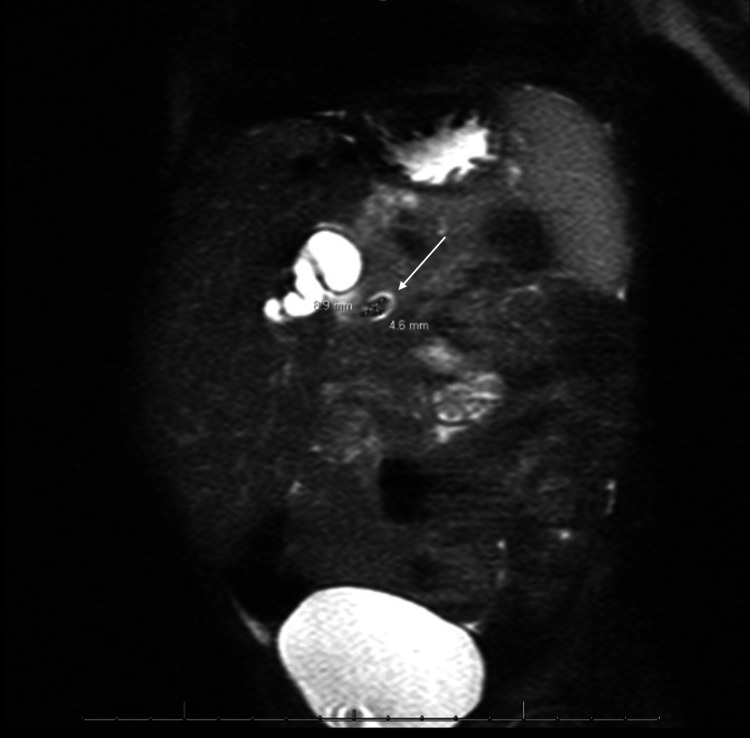

After admission, the patient was started on ursodiol, piperacillin-tazobactam, and maintenance intravenous fluids containing dextrose. A nothing by mouth (NPO) order was also placed in preparation for imaging under sedation. The following morning, MRCP was completed, showing the common hepatic duct measuring 13 mm and a 9×5 mm stone in the distal common bile duct (Figure 2).